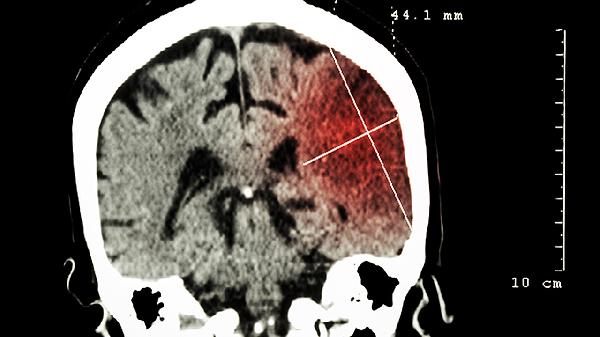

脑震荡或中风造成的胼胝体损伤会中断左右脑信息传递,表现为肢体动作与思维不同步。康复阶段需进行双侧肢体协调训练,使用计算机辅助认知康复系统,配合神经营养药物如胞磷胆碱。